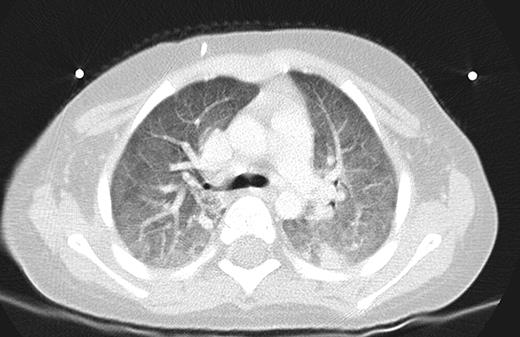

Our Patient, 8 weeks into chemotherapy for newly diagnosed ALL, presented with high grade fevers and poor activity. Patient was admitted 3 weeks prior for Bacillus cereus bacteremia. Additionally the patient had been on broad spectrum antibiotics on 2 occasions for febrile neutropenia episodes within the past 2 weeks. Patient had minimal respiratory symptoms at this presentation and recovered from pancytopenia at the time of this presentation. CT scans and chest x-ray (Figures 1 and 2) showed diffuse marked ground glass opacities with dependent consolidation in the lungs. On day 3 of admission, bronchoalveolar lavage (BAL) was preformed and empiric trimethoprim-sulfamethoxazole was initiated in addition to broad spectrum antibacterial, antifungal and antiviral medications.